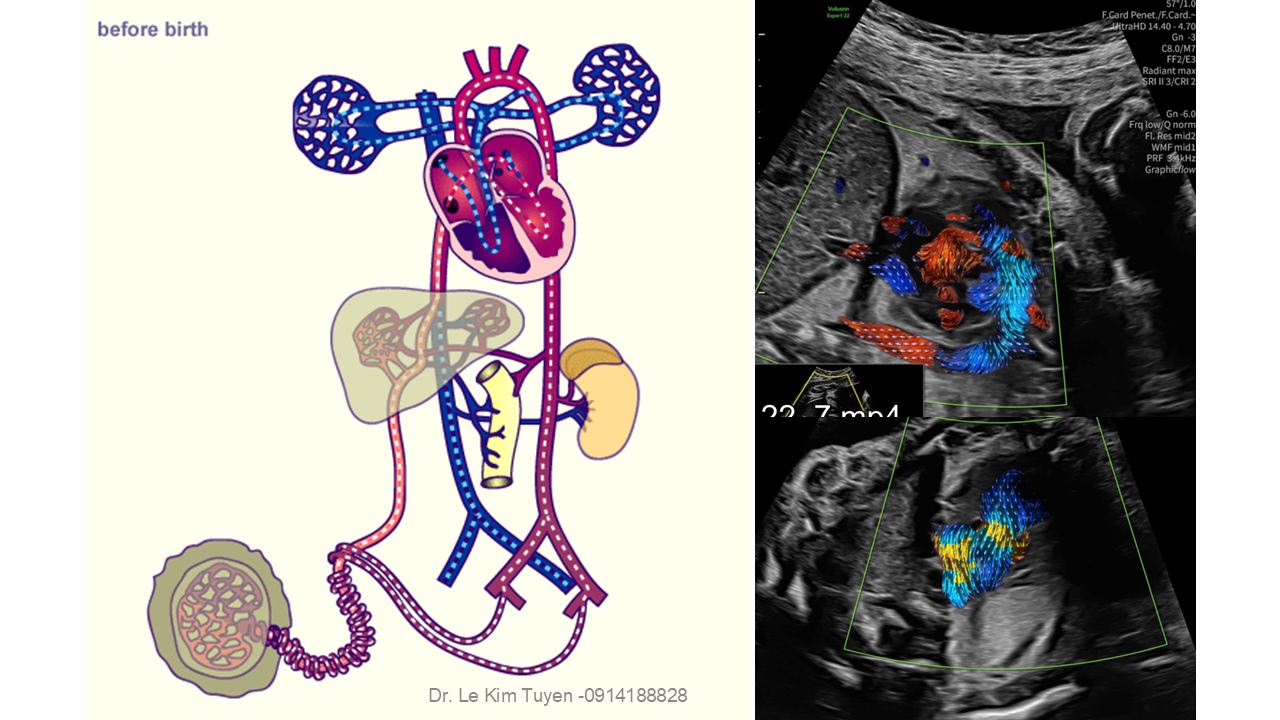

Áp dụng công nghệ Graphicflow trong phát hiện bệnh tim bẩm sinh cần cấp cứu sơ sinh

TS. BS. Lê Kim Tuyến

Bệnh viện Tim Tâm Đức